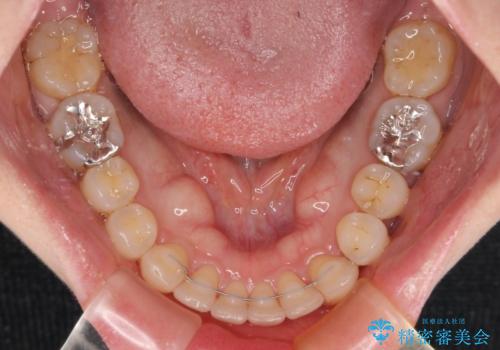

- 3年4ヶ月

インビザラインにて抜歯矯正を行うと、高頻度で奥歯が咬み合わなくなります。

また、抜歯スペースに向けて奥歯が移動する際、必ず傾斜して移動するため、仕上がりの咬み合わせはワイヤー矯正と比べて明らかに劣ります。

抜歯スペースが閉じてからも咬みにくさ改善のためマウスピース矯正を継続するため、治療期間は長期化します。